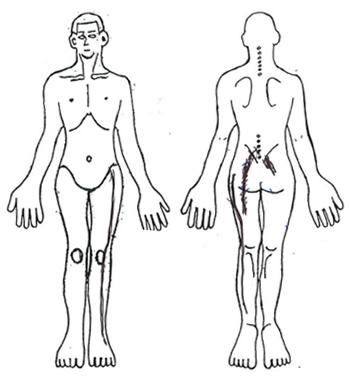

When she went up and down stairs more than 7 steps, she felt pain in her left low back. 20 minutes uphill, she felt pain in her left low back. She felt pain in 2 to 3-minute half-standing. Crouching posture is normal, and she can sit in a chair for 1 hour.

Figure 2-5. Findings in the lower back and lower extremities